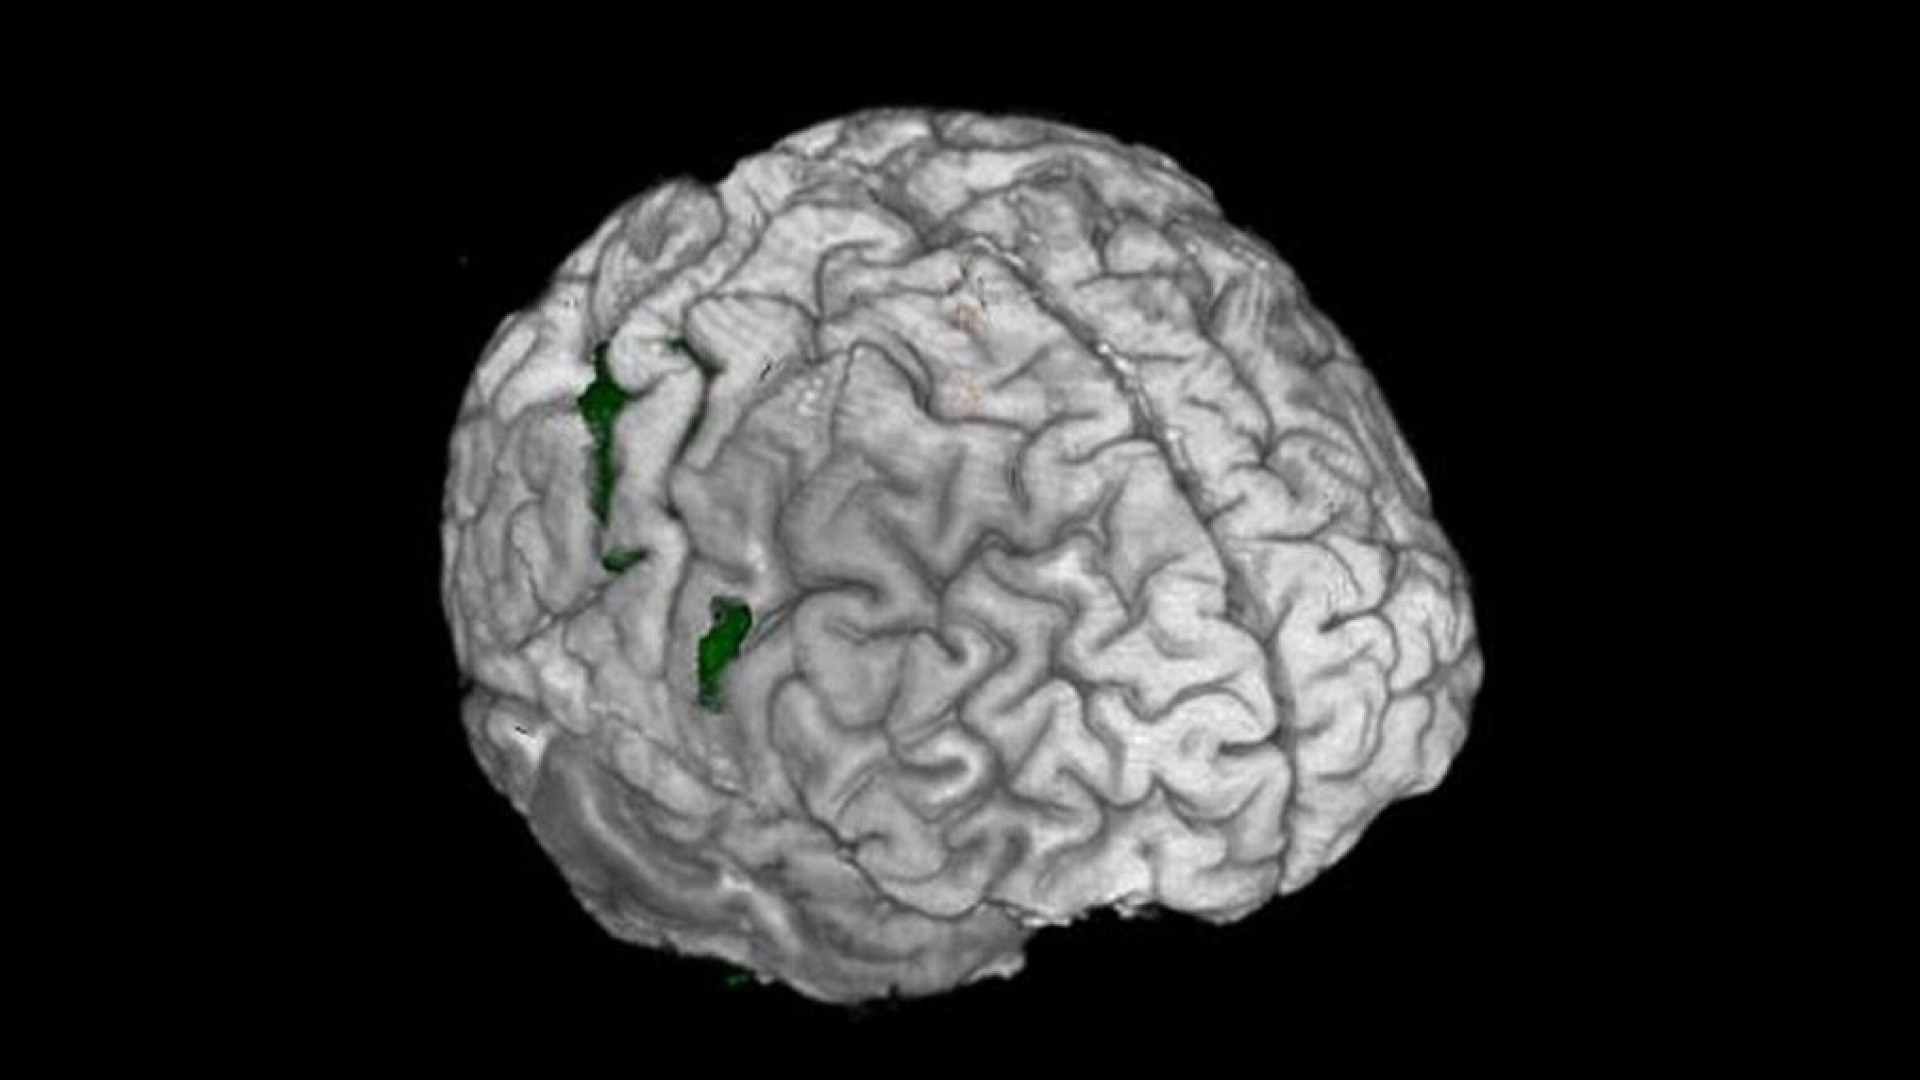

- Sophisticated visualization techniques that fuse analysis results with anatomical data

- Clear visualization with color activation maps and interactive thresholding